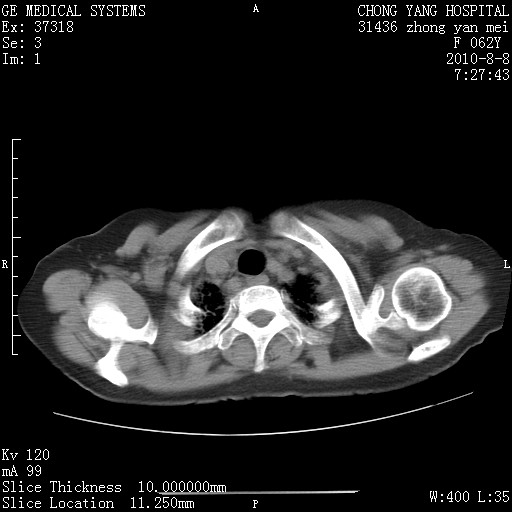

1.肺间质纤维化.

2.纵隔淋巴结肿大。

3.迷走右锁骨下动脉。